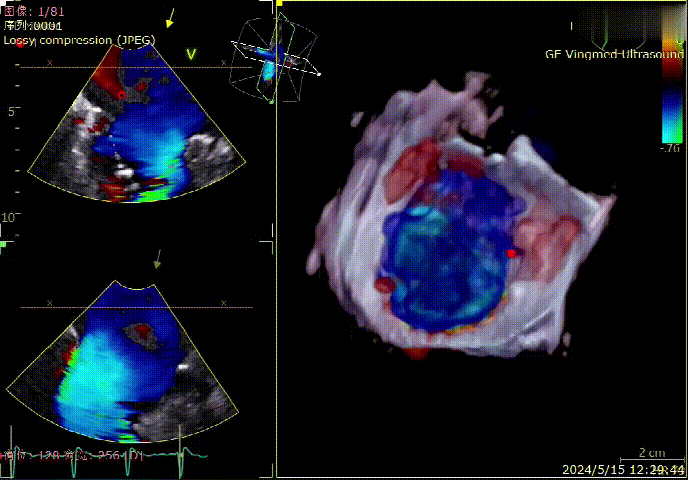

术前3D

术前3D color